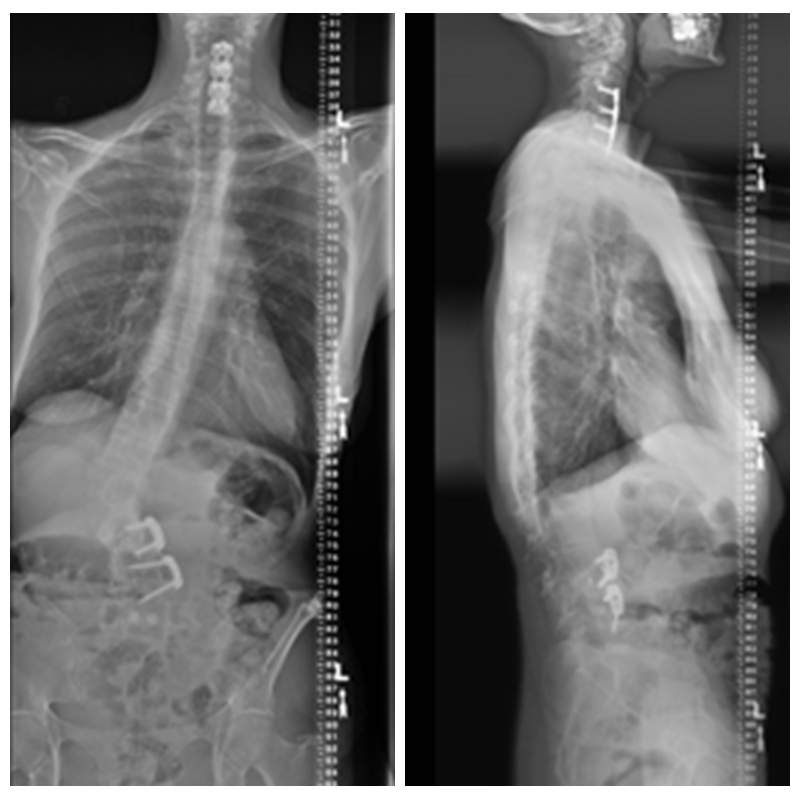

术前X线

术后X线